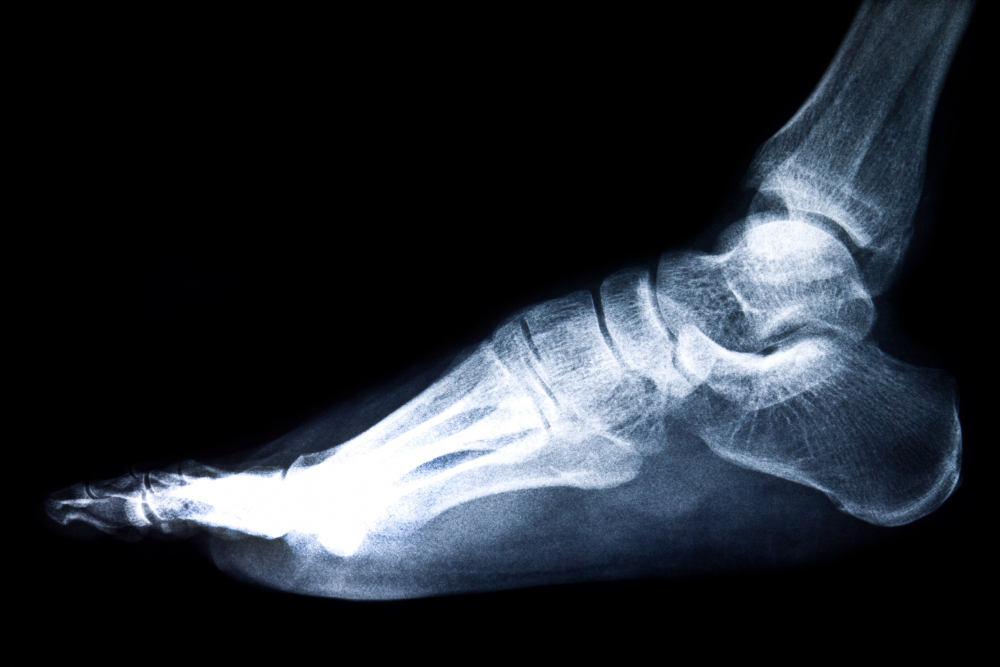

X-RAY RIGHT HEEL LAT/AXI is a specialized radiological imaging test used to evaluate the heel bone (calcaneus) of the right foot. This test includes lateral (LAT) and axial (AXI) views, allowing doctors to examine the heel bone from different angles. It plays a crucial role in diagnosing heel pain, fractures, deformities, infections, and degenerative conditions.

At Diagnopein Diagnostic Center in Nashik, X-RAY RIGHT HEEL LAT/AXI is performed using advanced digital X-ray equipment to ensure accurate imaging with minimal radiation exposure. This test is commonly advised for patients experiencing chronic heel pain, swelling, difficulty walking, or post-injury assessment.